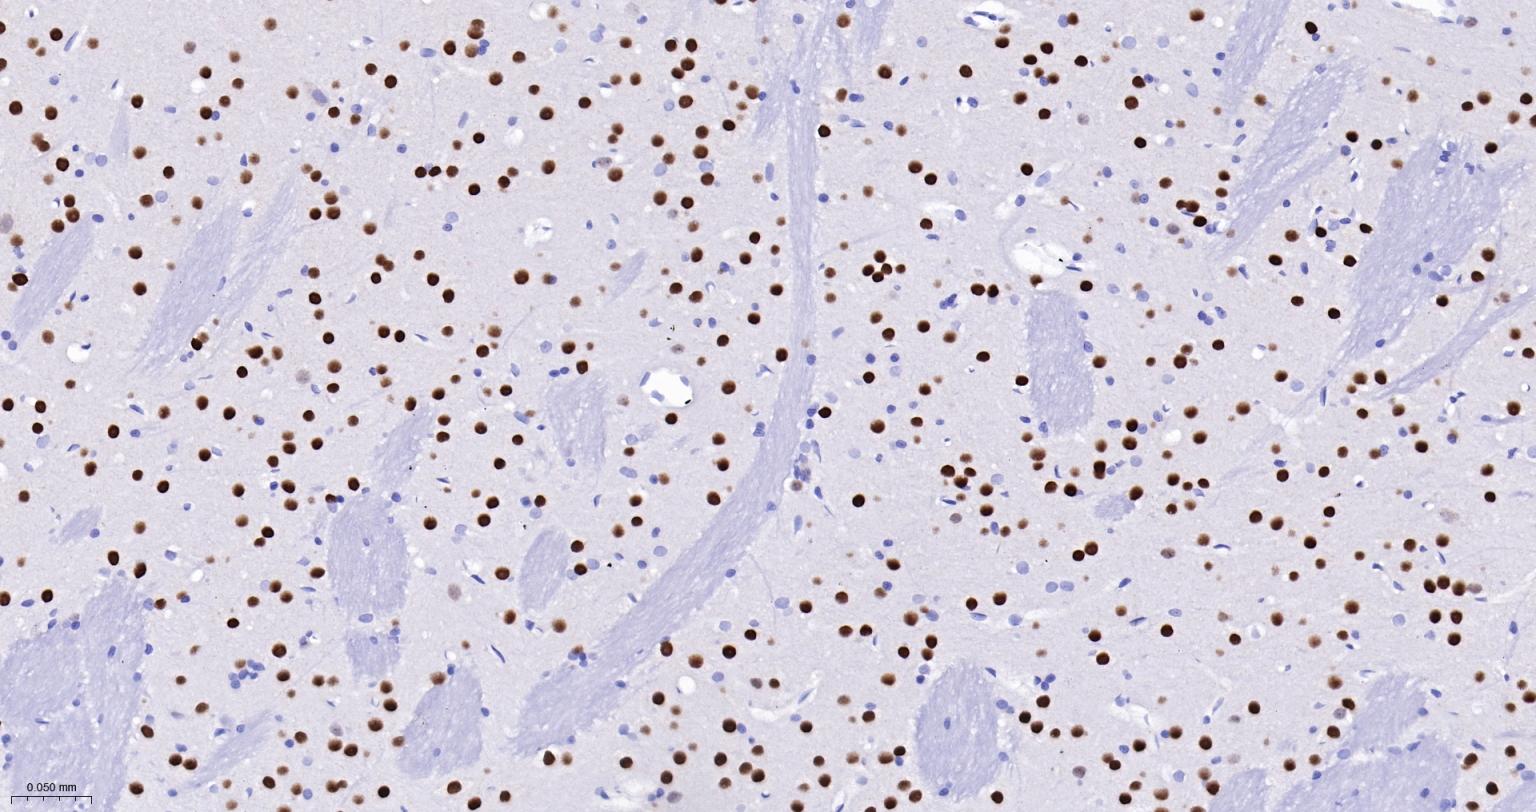

Paraformaldehyde-fixed, paraffin embedded Rat Cerebrum; Antigen retrieval by boiling in sodium citrate buffer (pH6.0) for 15 min; The section was incubated with Ctip2 Monoclonal Antibody, Unconjugated (bsm-61400R) at 1:300 overnight at 4°C, followed by conjugation to the bs-0295G-HRP and DAB (C-0010) staining.